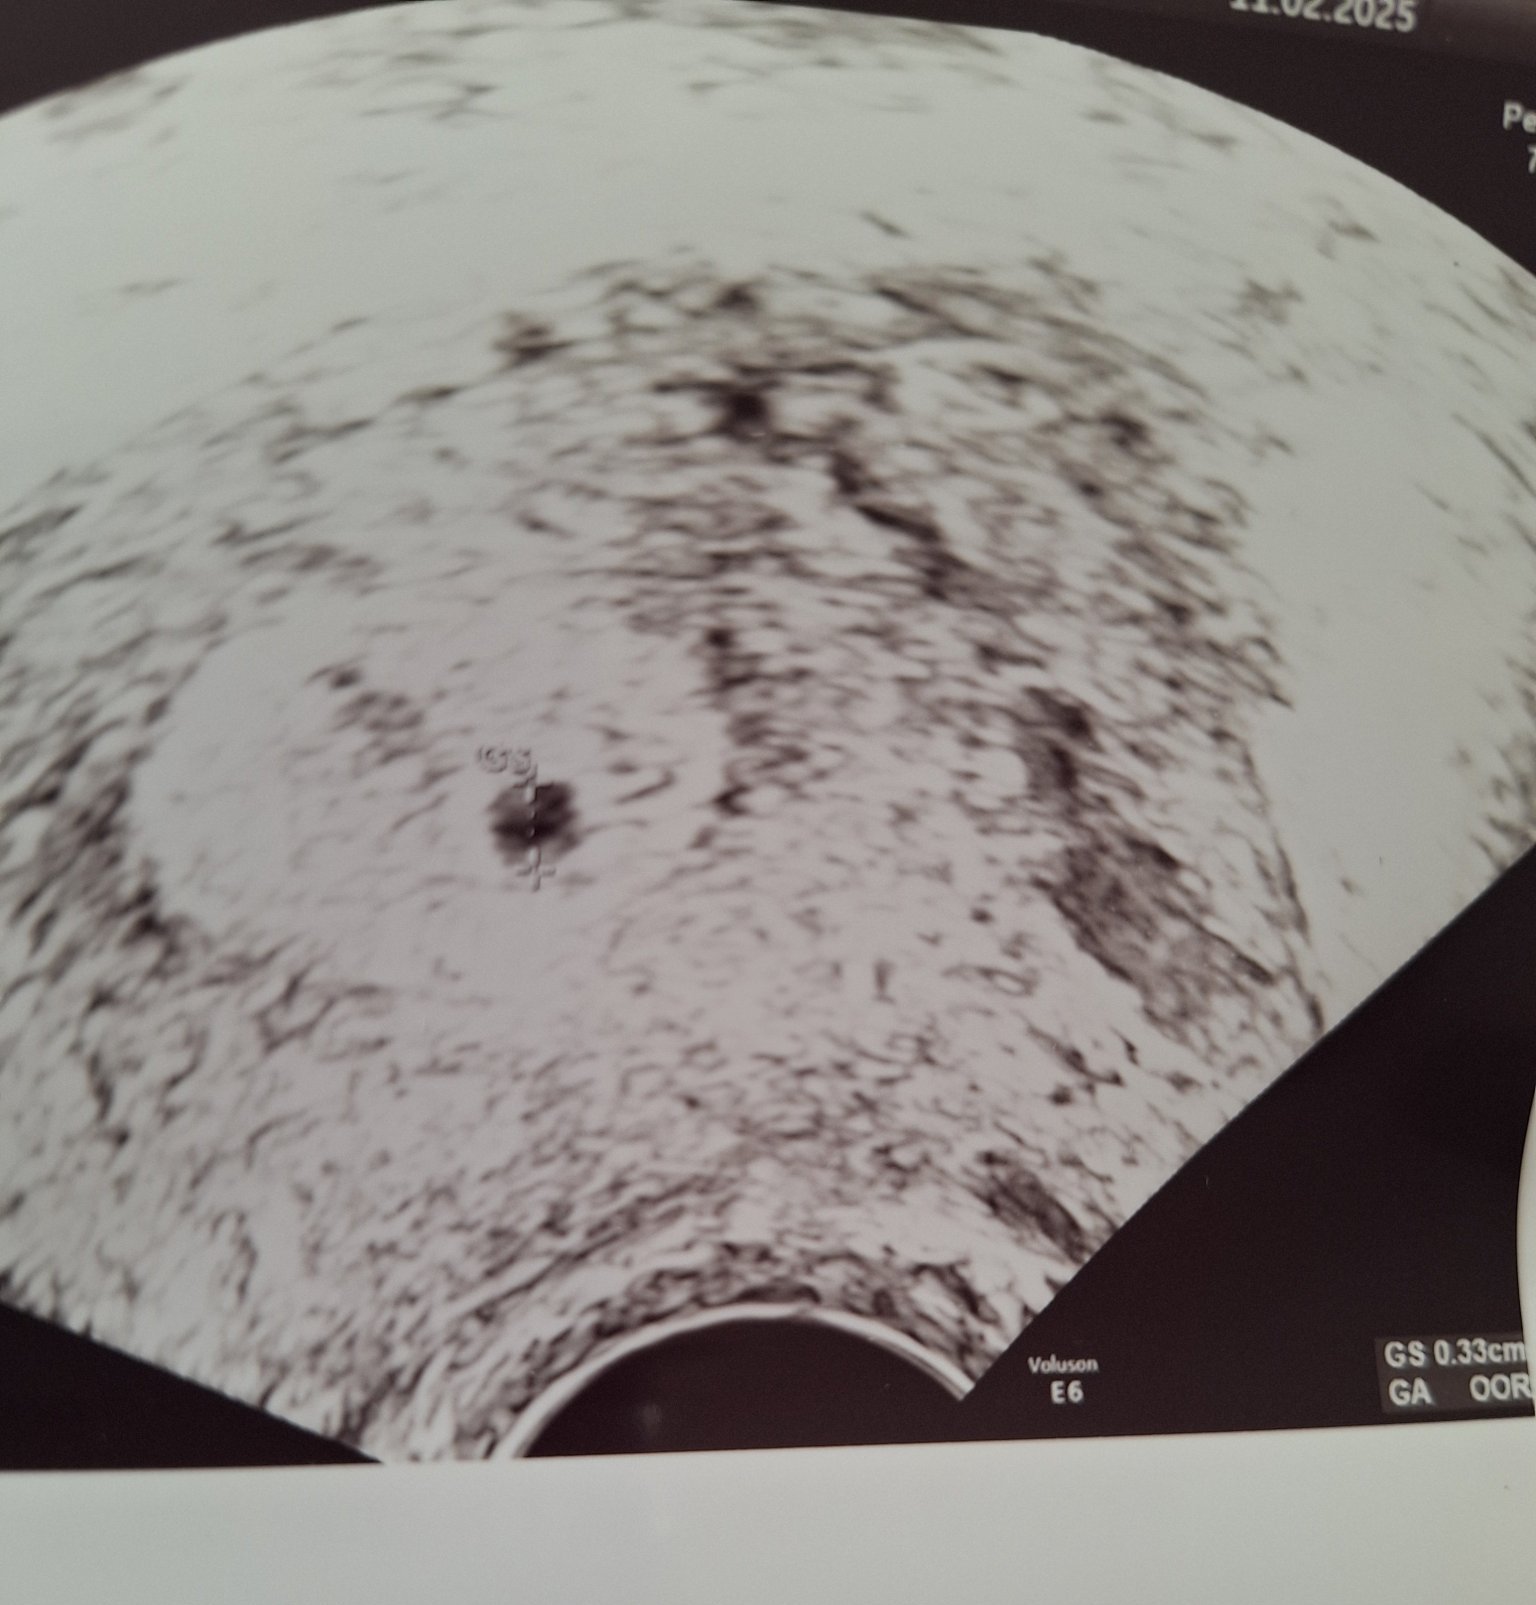

Връщам се от прегледа, видя се сак в матката и задържан фоликул в дясно. Още е празен, нещо не и хареса май първоначално,  но ще се видим след 2 седмици за пулс(трябва да ходя другаде май или да чакам до началото на март). Отговаряло на 5 гс горе долу, аз така или иначе съм в 4 + 5 по мои сметки. Като цяло не се успокоих достатъчно, АГ ще отсъства и се чудя за пулса при Калчев ли да ходя или другаде.. направо още не съм решила нищо. Те от МЦ така и не ми върнаха отговор и се чудя да пиша ли пак.

За задържания фоликул нищо не говорихме, само че ще се резорбира.. и за него се притесних